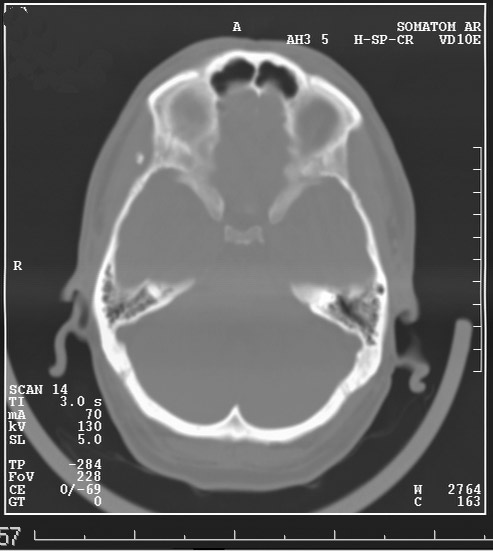

Выкладываю данные КТ

На снимке утолщение веретенообразное мышечного слоя с наличием кальцификатов(два) Кальцификаты в мышце чаще встречаются при паразитарных инфекциях(трихиниллез,токсоплазмоз,цистецеркоз),но их больше по количеству и в разных местах.Оссифицирующий миозит-имеет свою картину и распространение.Насчет Хортона-навряд ли,это же поражение сосуда.Насчет тофусов-они содержат ураты,чаще локализуются подкожно(не в мышце),при подагре осификации вдоль сухожилий.А может был удар,гематома с частичной кальцификацией?

Плотность не соответствует дроби, она более денсная и даёт артефакты.